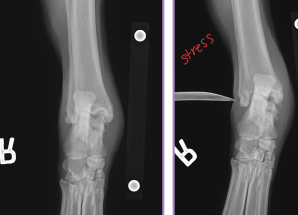

Fracture Classification

Location:

Spine, skull, joints: require special imaging (CT, oblique, stress views)

Long bones: Epiphysis, Physis (growth plate), Metaphysis, Diaphysis, Articular

Describe the Fracture

Forces: Tension, compression, bending, torsion, shear

Pattern: Transverse, Oblique, Spiral, Comminuted